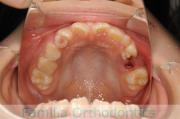

- ≫治療前

-

上顎

下顎

- ≫治療後